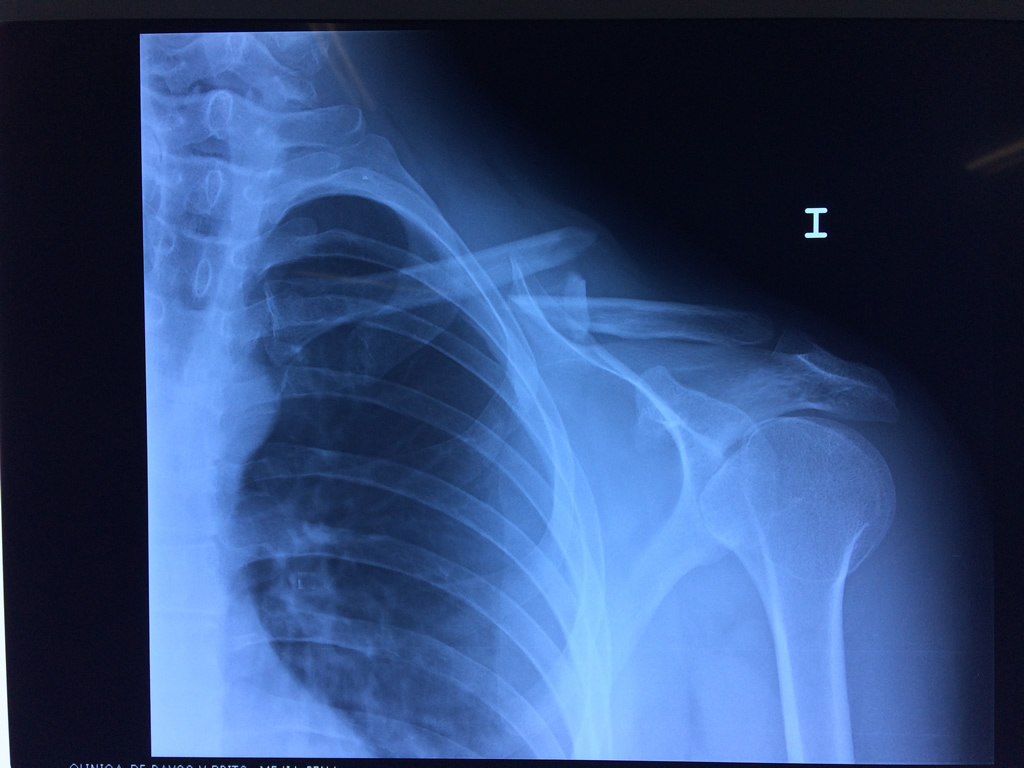

Clavicula 1

Detail Download